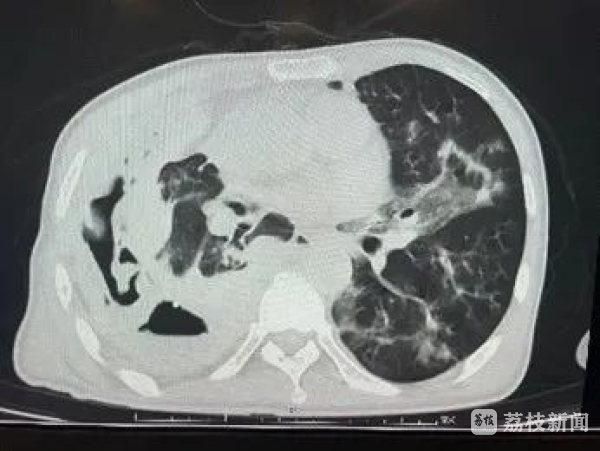

明确感染源后,临床医生对陈先生给予对应的抗感染治疗。经过治疗,陈先生的左肺感染性病变较前有局部吸收的好转迹象。

治疗两周后,胸部CT显示病情好转